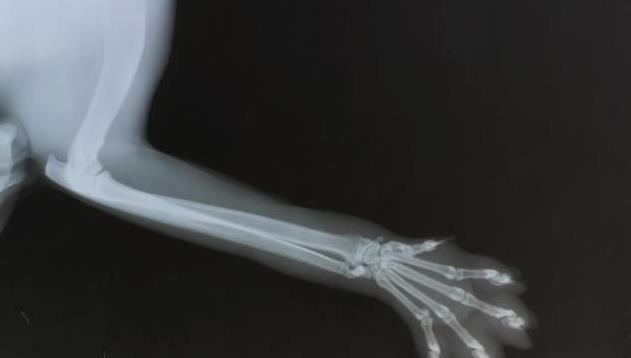

5个月大的肥大性骨营养不良的大丹犬尺骨X光片

肥大性骨营养不良也称为骨骼坏血病,Barlow氏病或Moller-Barlow氏病。最早是在1930年代中期的文献记载中出现。发病部位通常集中在桡骨、尺骨周围的生长板和胫骨等长骨的干骺端。尽管它主要只影响前两条腿,但也有可能发生在爪子,肋骨和下颌中。

X光线通常显示病变骨头的变化,例如与生长板平行线的外观,骨密度的变化以及生长板周围的钙化。